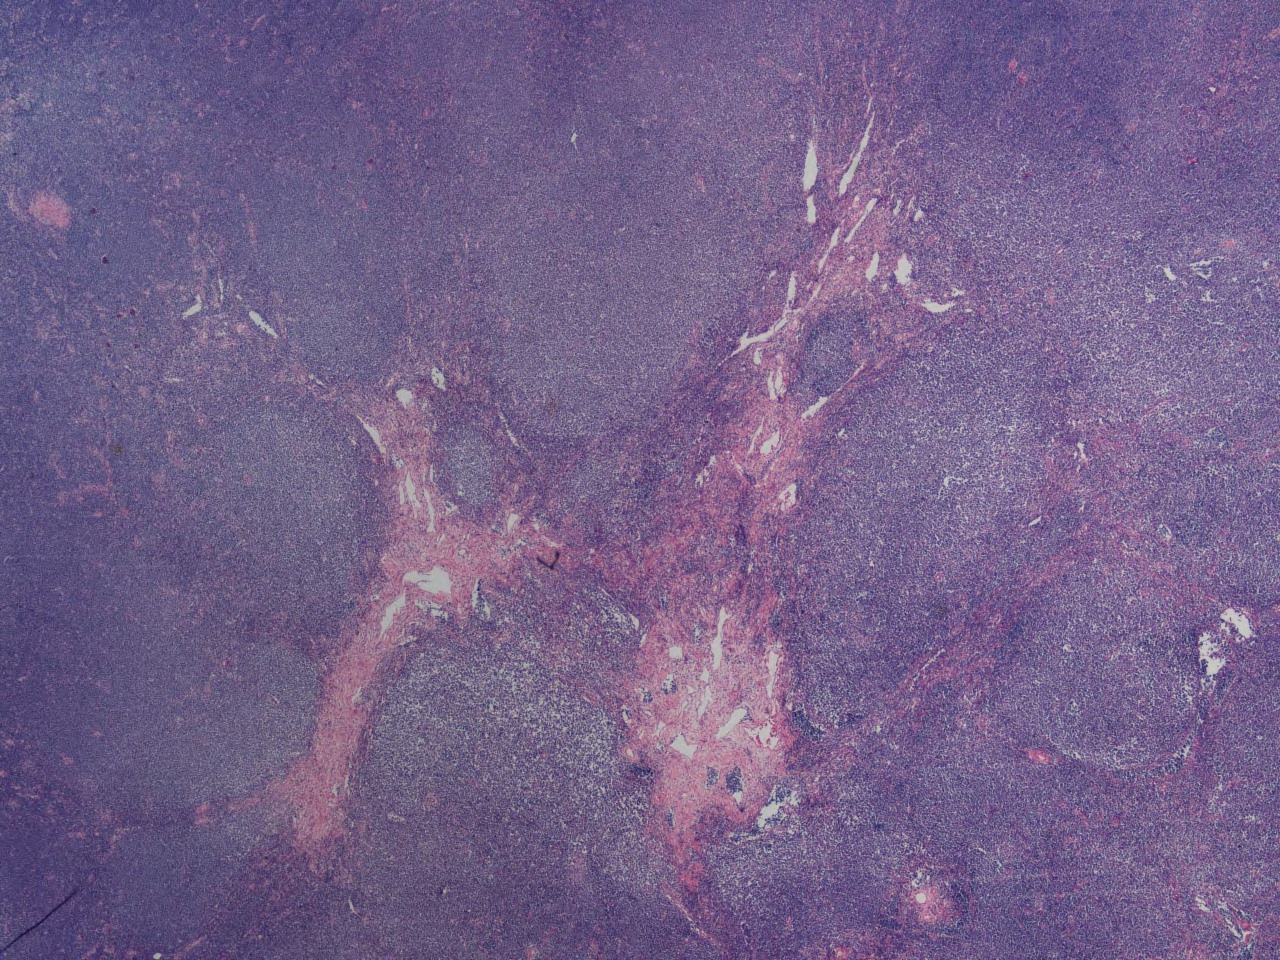

조직학적 소견생검 조직에서 관찰되는 MCL의 성장 패턴은 다음과 같이 나눌 수 있다.[7]

- 미만형(diffuse pattern): 림프종 세포가 림프절 전체에 퍼져 정상적인 림프절 구조가 사라진 형태이다. 가장 흔한 패턴이다.

- 결절형(nodular pattern): 림프절 내에 배 중심(germinal center)이 보이지 않는 MCL 세포로 이루어진 큰 결절들이 나타난다.

- 외투대형(mantle zone pattern): 정상적인 배 중심 주변의 외투대(mantle zone)가 림프종 세포로 인해 확장된 형태이다.

- 상피내형(in situ pattern): 림프종 세포가 외투대 내에 국한되어 있으며, 외투대의 확장은 보이지 않는다. 초기 단계의 병변으로 간주될 수 있다.

조직학적으로 전형적인(고전형) MCL은 작거나 중간 크기의 림프구로 구성되며, 세포질은 옅고 핵에는 뚜렷한 갈라짐(cleavage)이나 핵소체가 잘 보이지 않는 것이 특징이다.[7] 이러한 세포들이 균일하게 증식하여 단조로운 모습을 보이는 경우가 많다. 이는 아폽토시스(세포 자살)에 빠진 림프구를 처리하는 큰포식세포(tingible body macrophage)가 거의 없고, 세포 분열상이 드물기 때문이다.

MCL은 다음과 같은 조직 형태학적 아형으로 나눌 수 있다.

- 고전형(classical type): 위에서 설명한 전형적인 형태이며, MCL의 약 90%를 차지한다.

- 소세포 아형(small cell variant): 만성 림프구성 백혈병/소 림프구 림프종(CLL/SLL)과 유사하게 작은 림프구로 구성된다.

- 모구형 아형(blastoid variant): 림프모구 백혈병/림프종과 유사하게 핵이 둥글고 염색질이 미세하며 뚜렷한 핵소체를 가진 미성숙한 세포 형태를 보인다.[7]

- 다형성 아형(pleomorphic variant): 핵의 크기와 모양이 다양하며, 일부는 쪼개진 형태를 보인다. 크고 비정형적인 세포가 많아 미만성 거대 B세포 림프종(DLBCL)과 혼동될 수 있다.[7]

모구형 및 다형성 아형은 고전형 MCL보다 더 공격적인 경과를 보이는 경향이 있다.[7]